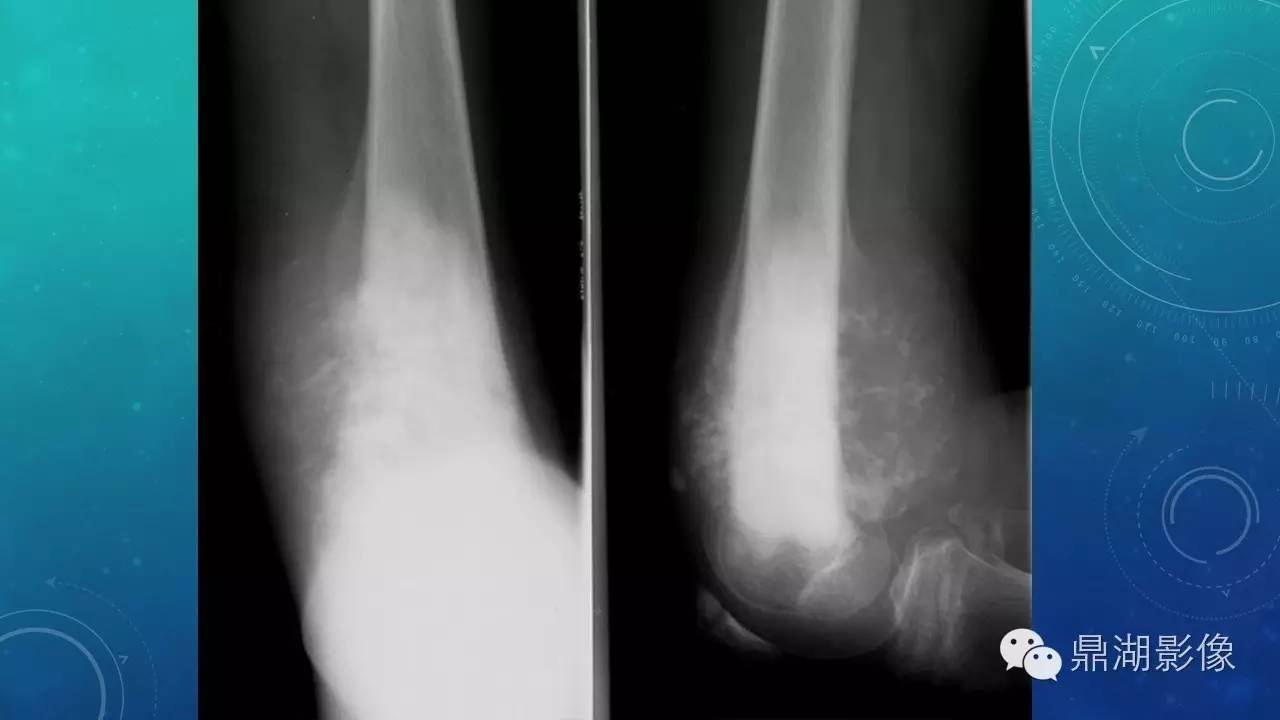

软组织钙化(的鉴别)